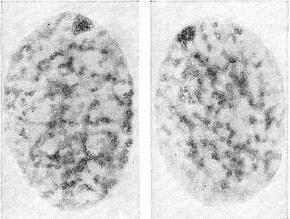

Статевий хроматин - особливі хроматиновые тільця клітинних ядер особин жіночої статі у людини та інших ссавців. Розташовуються біля ядерної оболонки, на препаратах зазвичай мають трикутну або овальну форму; розмір 0,7-1,2 мк (рис. 1). Статевий хроматин утворений однією з Х-хромосомах жіночого каріотипу і може бути виявлений у будь-якої тканини людини (в клітинах слизових оболонок, шкіри, крові, биопсированной тканини), Найбільш простим дослідженням статевого хроматину є дослідження його в клітинах епітелію слизової оболонки порожнини рота. Взятий шпателем зішкріб зі слизової оболонки щоки поміщають на предметне скло, фарбують ацетоорсеином і аналізують під мікроскопом 100 светлоокрашенных клітинних ядер, підраховуючи, скільки з них містять статевий хроматин. В нормі він зустрічається в середньому на 30-40% ядер у жінок і не виявляється у чоловіків (рис. 2).

![]() Рис. 1. Ядра, що містять статевий хроматин (зішкріб зі слизової оболонки порожнини рота здорової жінки).  |